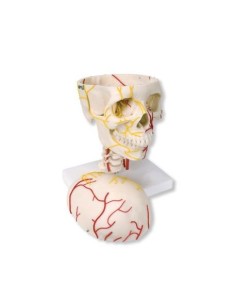

Dal cranio in 22 parti con incastri magnetici ai modelli di colonna vertebrale, da quelli di articolazioni a quelli di cuore, ogni pezzo della nostra collezione è progettato per un’immersione totale nello studio dell’anatomia umana. I nostri modelli, realizzati tramite scansioni di ossa vere, garantiscono un’esperienza tattile autentica e una fedeltà di peso quasi identica agli originali.

Essenziali per studenti e professionisti, i nostri modelli anatomici sono strumenti didattici che permettono di osservare le strutture anatomiche con precisione, eliminando la necessità di dissezioni o studi invasivi. Sono inoltre utili per spiegare ai pazienti le patologie, rendendo la comunicazione più efficace e risparmiando tempo prezioso.